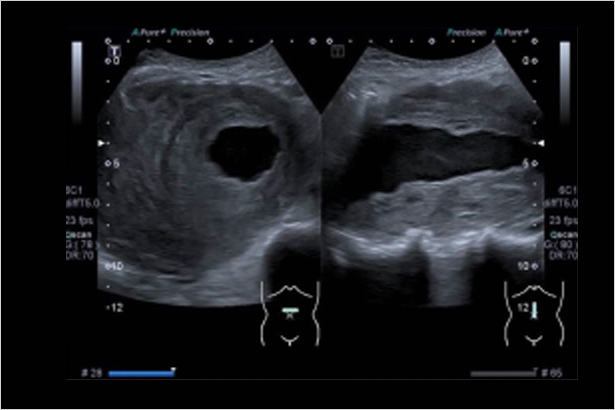

波束發射和采集技術,解決分辨力和穿透力的矛盾,同時提高圖像質量和穿透深度

獨有信號增強技術,通過處理波束之間的信息,提升信號強度,提升圖像質量

收集不同方向的回波所帶來的多層次信息進行成像,減少偽影及斑點噪聲